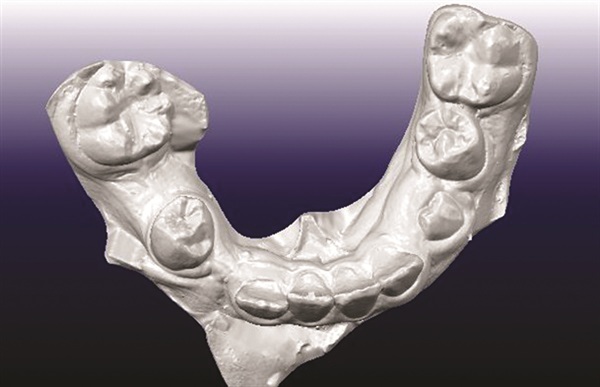

A 12-year-old male presented with severe Class II, deep bite, and significant crowding. The original poster was torn between two conflicting clinical pictures. Half the diagnostic findings pointed toward extraction: second molars impacted in the ramus, a blocked lower left canine, blocked maxillary canines, and a nearly full-step Class II relationship. The other half suggested non-extraction with vertical control to avoid deepening the bite further. The concern was that by the time crowding was resolved and the deep bite corrected, the incisors would be too flared for effective Class II correction without further proclination. The question posed to the forum was whether immediate upper first premolar and lower second premolar extractions were the best route forward (Figs. 1–11).

Once better records were available, opinion shifted strongly toward rapid palatal expansion as a necessary first step. Several contributors noted the obvious transverse deficiency and recommended expansion before making final decisions about which teeth to extract. Some leaned toward extracting second premolars even in a Class II case, while others preferred a non-extraction approach if feasible.

The most frequently suggested treatment involved rapid palatal expansion followed by a Herbst appliance. Several clinicians viewed this as an ideal growth modification case given the patient’s age, low mandibular plane angle, and Class II presentation. Expansion would address the transverse deficiency first, with Herbst therapy used to advance the mandible and distalize the maxillary segment while creating space for the blocked canines. Because the lower incisors were upright and the patient exhibited a low-angle pattern, contributors felt the lower arch could tolerate some proclination. Opinions varied on lower appliance design, with some recommending premolar crowns and lingual arch support to help manage canine alignment while minimizing unwanted incisor effects.